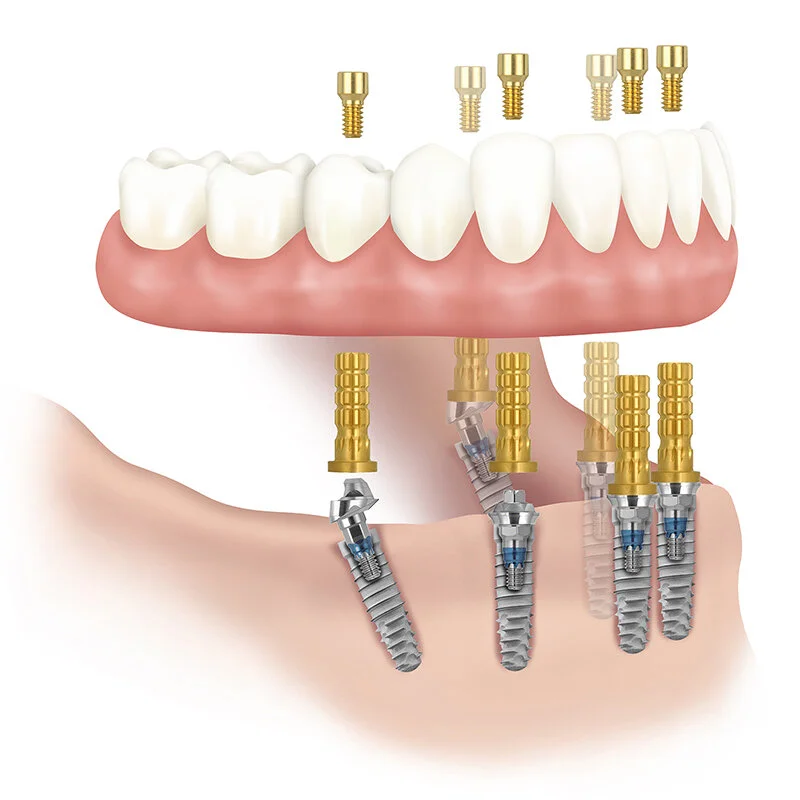

![Edentulous jaw with prothesis and implants]()

Edentulous jaw with prothesis and implants